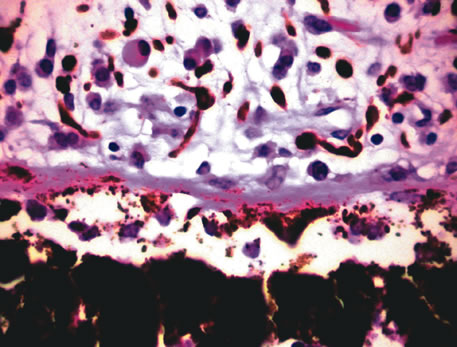

Inflammatory conditions may also lead to iris nodules. Patients suffering from fungal endophthalmitis may demonstrate an irregular yellow-white mass on the iris. Histologically, these appear as necrotizing granulomas containing mycotic agents (Fig. 2). In juvenile xanthogranuloma, a yellowish-gray iris lesion may be associated with spontaneous hyphema, and histopathologically the nodules demonstrate diffuse histiocytic infiltrate (Fig. 3). Multinucleated giant cells displaying peripheral foamy cytoplasm are also noted; these cells are known as Touton giant cells.29 The giant cells and the histiocytes contain lipid that can be demonstrated by oil red O stain.

Fig. 3. Juvenile xanthogranuloma. The iris is infiltrated by histiocytes, which form nodular aggregates on the anterior surface of the iris. (Hemotoxylin-eosin ×25.) Inset (×200) shows oil red O-positive histiocytes.